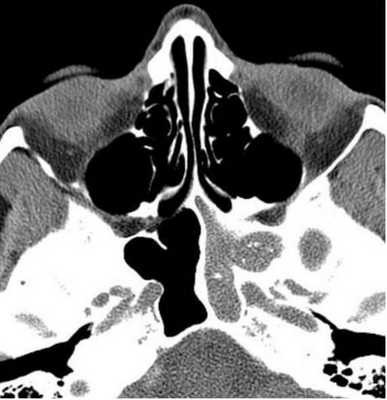

Правосторонний этмоидит (стрелка). КТ. Фронтальная плоскость.